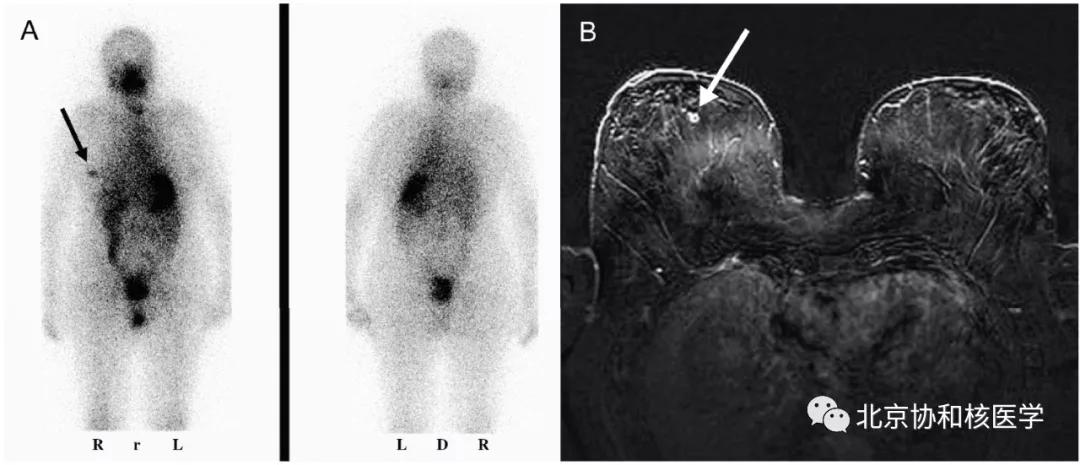

乳腺良性纤维瘤碘摄取:

鼻骨骨样骨瘤所致碘摄取,腹部另可见由于巨大肾囊肿所致碘异常摄取: